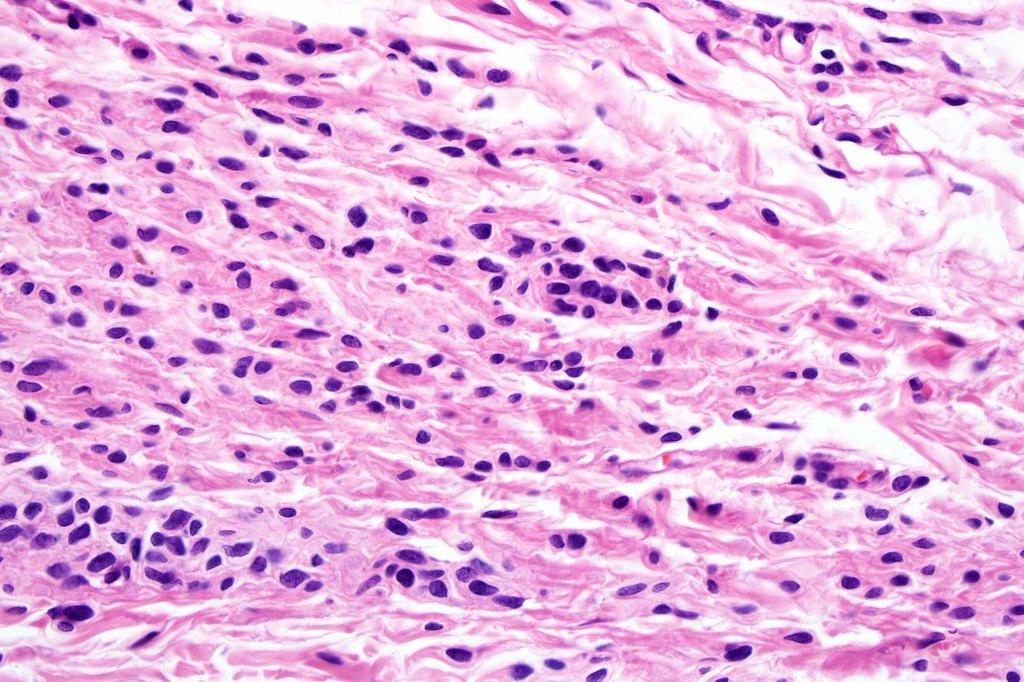

•Spindle cell, small blue cell, blue nevus-like features, Spitzoid & proliferative nodules with mesenchymal differentiation (myofibroblastic, chondroid & osteoid) can be seen

•The nodule generally merges with the adjacent nevus but sometimes it can be sharply circumscribed

•It is hypercellular and most often composed of epithelioid cells showing little pleomorphism & only occasional mitoses

•Some examples show more marked pleomorphism with prominent nucleoli and increased mitotic activity but abnormal mitoses are not a feature. These are not associated with any sinister biological potential